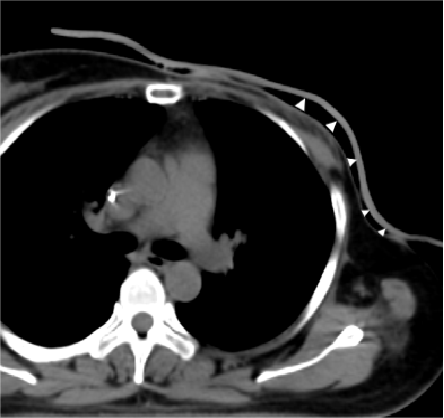

Conventional Bolus (white △ indicates air gaps)

3D Printed Bolus